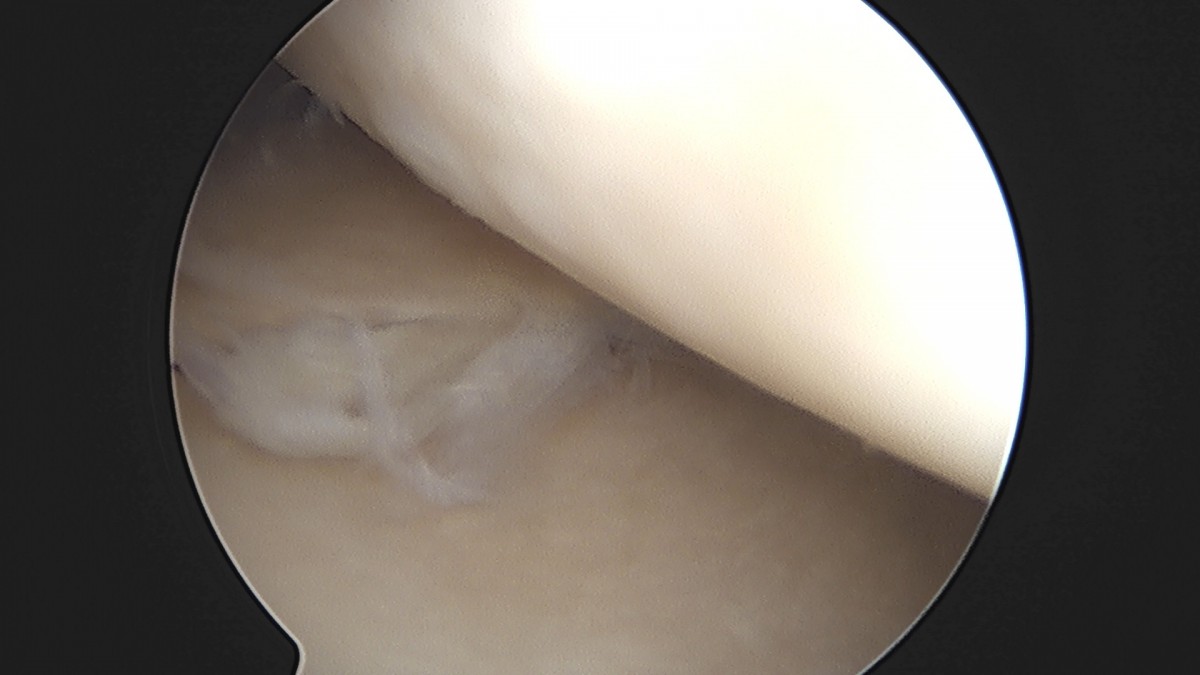

이재상원장님 무릎 반월상 연골판 절제술 고기O 환자

dae765e4d9ac96aee867c9d6292d8784_1758005092_2595.jpg